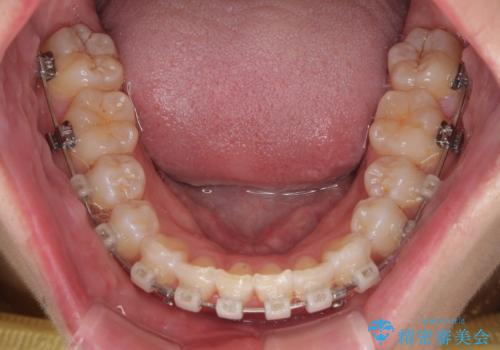

- 審美装置

- 2年2ヶ月

- 10-30回

なかなか舌の突出癖が改善できず、上下前歯が非接触となる期間が長く続きました。

アンカースクリューの活用と、舌のトレーニングを何度も指導し、出っ歯になることなく無事に治療を終えることができました。